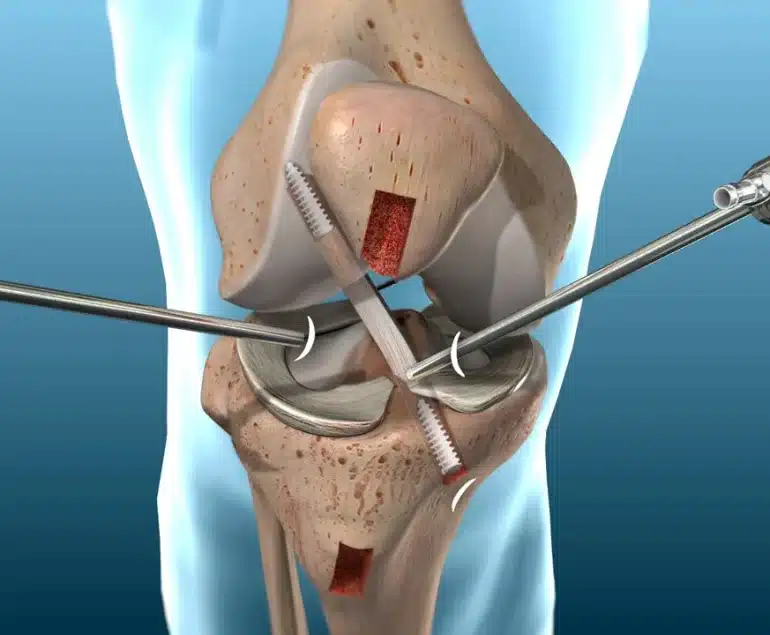

فيما يتعلق بعلاج تمزق جزئي في الرباط الصليبي، تتنوع الخيارات بين العلاج غير الجراحي والجراحة< حيث في الحالات البسيطة، يميل الأطباء إلى اتباع العلاج المحافظ، الذي يشمل فترة من الراحة، واستخدام الثلج، والعلاج الطبيعي لتحسين قدرة المريض على الحركة وتقوية العضلات المحيطة بالركبة؛ بينما في الحالات الأكثر خطورة، قد تكون الجراحة ضرورية لإصلاح الرباط؛ وتتفاوت فترة العلاج وفقا لشدة الإصابة، حيث يمكن أن تتراوح مدة التعافي من عدة أسابيع إلى عدة أشهر من المهم أيضًا التنويه إلى أن الرباط الصليبي لا يتجدد بشكل طبيعي بعد التمزق الجزئي، مما يبرز أهمية اتخاذ الإجراءات المناسبة للحفاظ على صحة الركبة وأدائها.